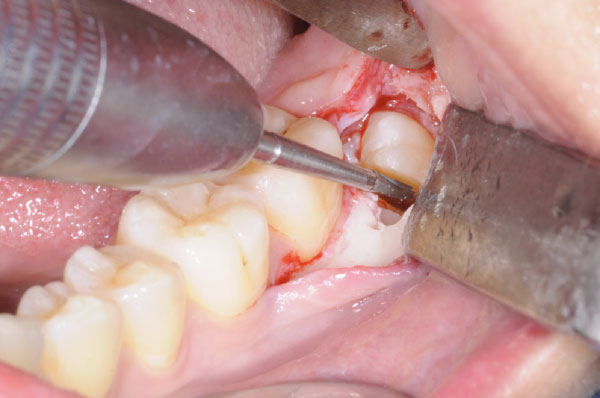

L'intervento segue precisi protocolli chirurgici. Dopo l'esecuzione di un'anestesia loco-regionale, si procede all'allestimento di un lembo di accesso mucoperiosteo a spessore totale, la cui scelta è determinata principalmente dalla profondità dell'inclusione e dalla posizione del terzo molare. In tutti i casi, il lembo deve creare un sufficiente accesso chirurgico (visivo e strumentale), evitare le strutture anatomiche circostanti (nervo linguale, arteria facciale), consentire un corretto riposizionamento del lembo e un'agevole sutura.

L'utilizzo dello strumentario piezoelettrico rappresenta una valida alternativa nei casi di ostectomia profonda e per l'avulsione di residui radicolari in stretto rapporto con strutture anatomiche nobili.

Poiché gli interventi di avulsione degli ottavi inferiori prevedono l'utilizzo di uno strumentario base per la chirurgia estrattiva e uno strumentario specifico per le manovre di ostectomia e odontotomia, sono anche forniti i criteri di scelta più adeguati per l'esecuzione dell'intervento, per la preparazione del paziente e dell'ambiente di lavoro.